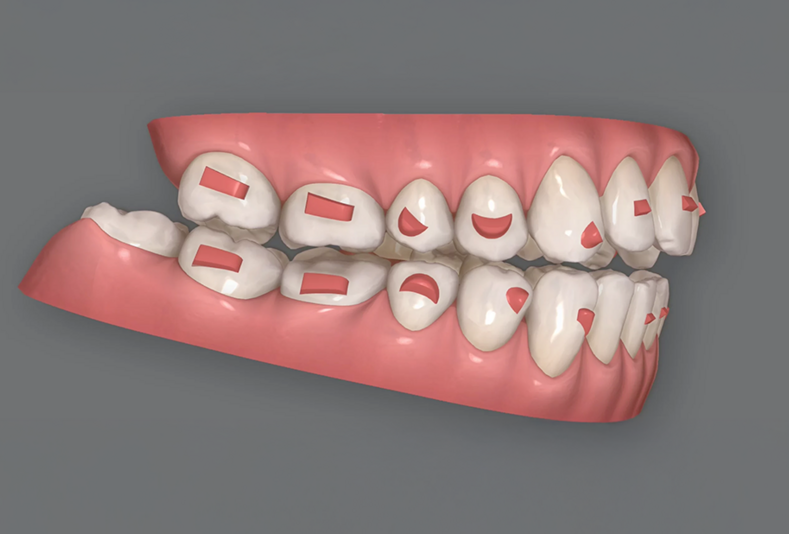

ClinCheck

Igiene dentale

Predicibilità di ClinCheck nella correzione dell'overbite con allineatori

13 Novembre 2025